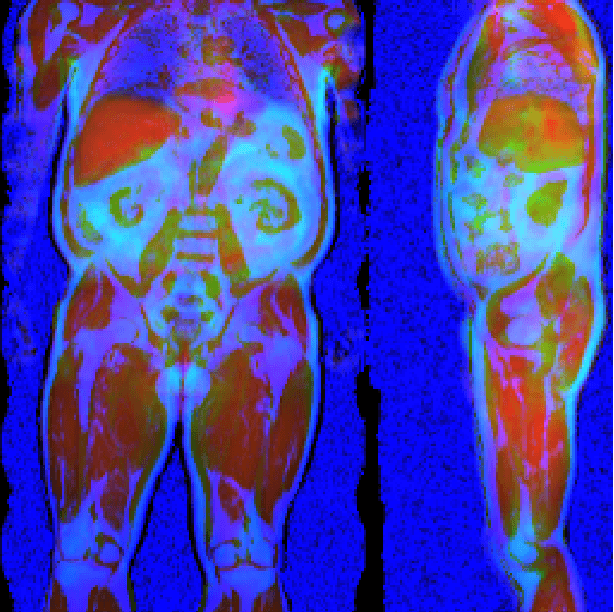

Abstract:Large-scale medical studies such as the UK Biobank examine thousands of volunteer participants with medical imaging techniques. Combined with the vast amount of collected metadata, anatomical information from these images has the potential for medical analyses at unprecedented scale. However, their evaluation often requires manual input and long processing times, limiting the amount of reference values for biomarkers and other measurements available for research. Recent approaches with convolutional neural networks for regression can perform these evaluations automatically. On magnetic resonance imaging (MRI) data of more than 40,000 UK Biobank subjects, these systems can estimate human age, body composition and more. This style of analysis is almost entirely data-driven and no manual intervention or guidance with manually segmented ground truth images is required. The networks often closely emulate the reference method that provided their training data and can reach levels of agreement comparable to the expected variability between established medical gold standard techniques. The risk of silent failure can be individually quantified by predictive uncertainty obtained from a mean-variance criterion and ensembling. Saliency analysis furthermore enables an interpretation of the underlying relevant image features and showed that the networks learned to correctly target specific organs, limbs, and regions of interest.